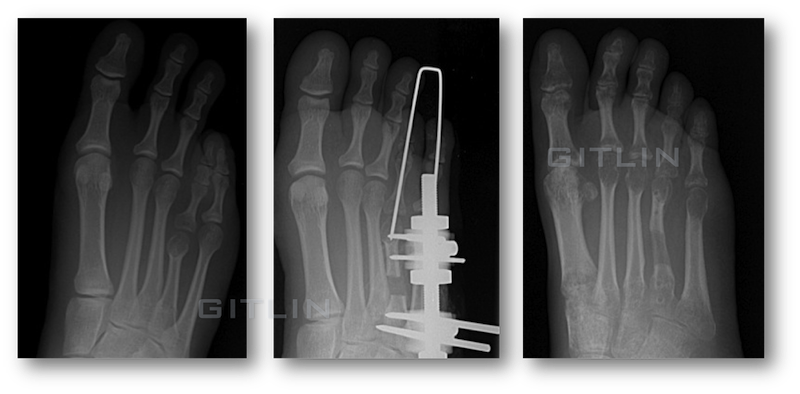

Below we see xrays of the process, on the left is a typical before surgery xray of a brachymetatarsia condition. The center image is during the lengthening, here you can see the bone regenerate in the middle of the bone. You can also see the xray of the metal external fixator with pins holding it onto the metatarsal bone. On the right is a final xray you can see the solidifying regenerate.